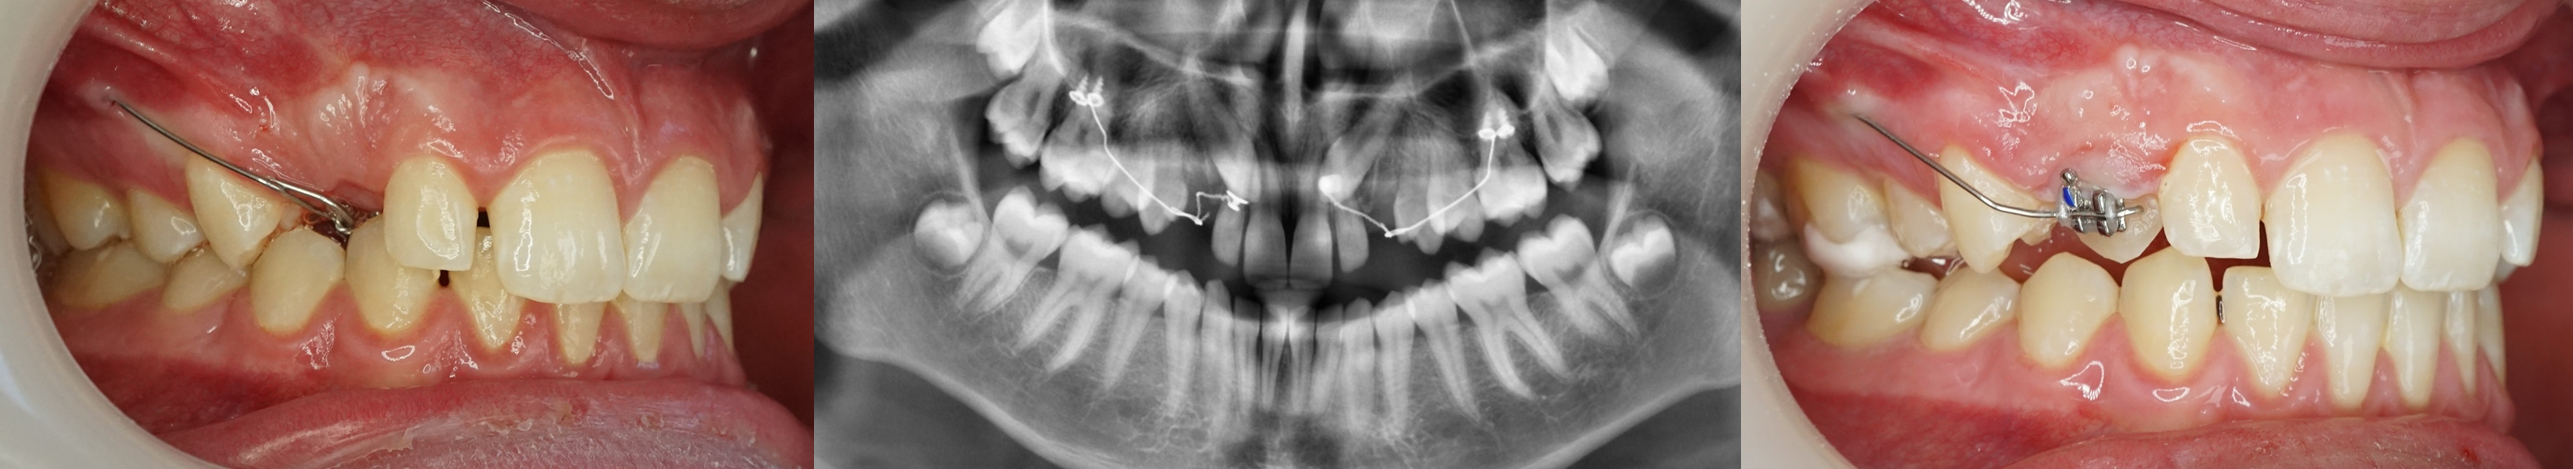

Le dégagement chirurgical de la couronne de la canine incluse vient d’être réalisé, la ligature accrochée au bouton collé à sa surface émerge à son emplacement naturel d’éruption.

Le lambeau d’accès à la canine a été refermé et suturé.

Le bras du CT8 est activé vers le bas pour une canine vestibulaire, vers l’extérieur pour une canine palatine. Il est replié sur lui-même et accroché à la ligature reliée à la canine au niveau de son espace naturel d’éruption.

Les deux seules actions à réaliser par la suite seront :

1. Le raccourcissement de la ligature au fur et à mesure du déplacement de la canine.

2. Le contrôle de la direction de la traction et son réajustement éventuel lors de la même opération.